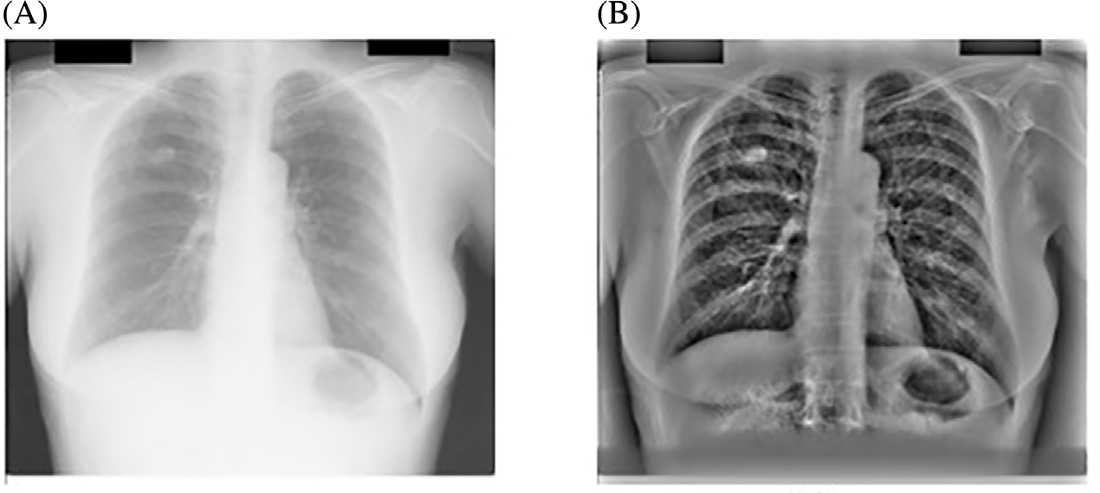

尽管胸部X光在临床日常中提供了重要的诊断检查,但由于相关诊断结构与无关的骨性结构重叠,使得影像较为复杂。因此,当前计算机辅助诊断系统(科皮尼、迪乔蒂、法尔基尼、维拉里和瓦利,2003年;吉格尔、土井、麦克马洪、梅茨和尹,1990年;德科宁等人,2013年;兰格、普拉特和因巴尔,1997年)在胸部X光片中面临的主要挑战是检测与肋骨、肋骨交叉及锁骨重叠的结节,如图14.1所示。这些骨性结构会导致大量的假阳性结果,正如凯瑟尔奇和吉田(2002年)所指出的

使用主成分分析滤波器进行肋骨抑制的结果如图14.2B所示。采用标准的高斯检测器高斯拉普拉斯掩模(LOG)来寻找可能存在结节的峰值区域。在原始胸部X光图像中应用该掩模导致了大量的假阳性,如图14.2A 所示,其中许多假阳性出现在肋骨上。